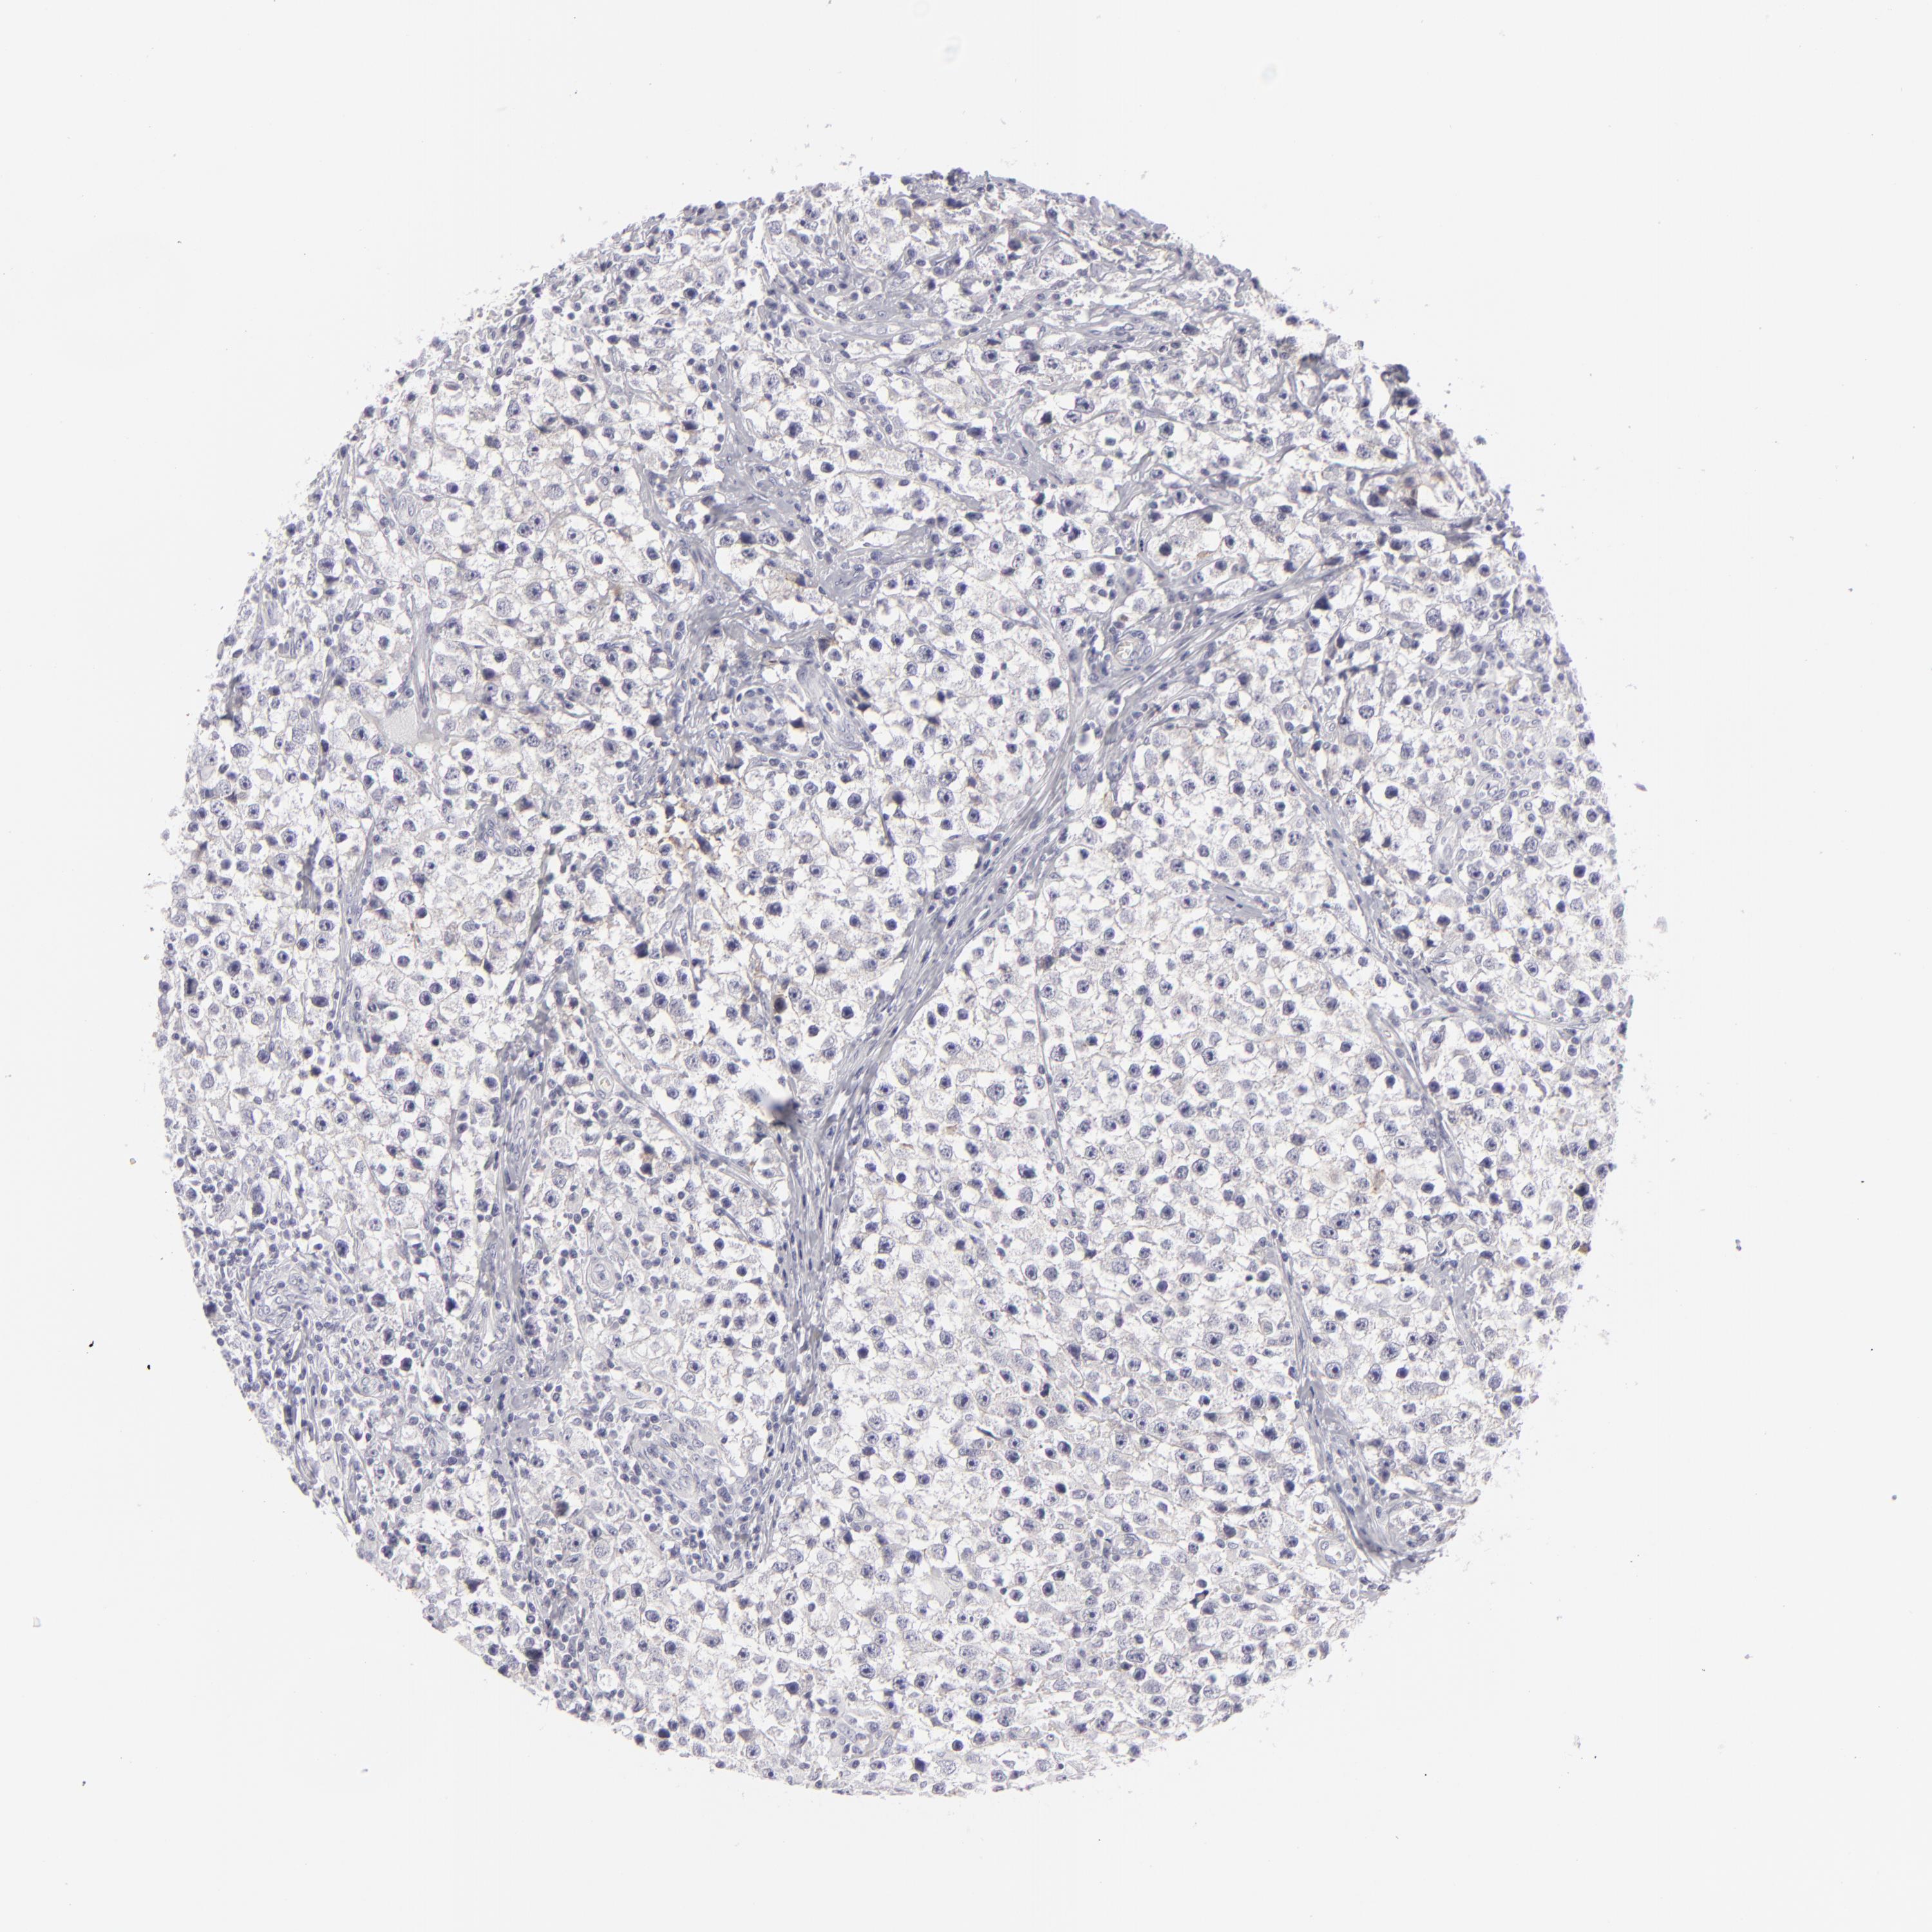

TESTIS CANCER - Protein expressioni

A mouse-over function shows sample information and annotation data. Click on an image to view it in a full screen mode. Samples can be filtered based on level of antibody staining by selecting one or several of the following categories: high, medium, low and not detected. The assay and annotation is described here.

Note that samples used for immunohistochemistry by the Human Protein Atlas do not correspond to samples in the TCGA dataset.

Antibody stainingi

Antibody staining in the annotated cell types in the current human tissue is reported as not detected, low, medium, or high, based on conventional immunohistochemistry profiling in selected tissues. This score is based on the combination of the staining intensity and fraction of stained cells.

Each image is clickable and will lead to virtual microscopy that enables deeper exploration of all samples and also displays staining intensity scores, fraction scores and subcellular localization as well as patient and tissue information for each sample.

Antibody HPA032047

Seminoma, NOS

Carcinoma, Embryonal, NOS